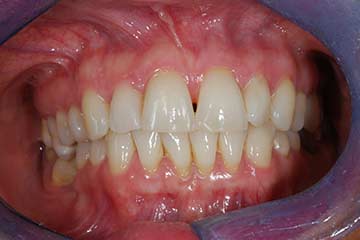

Con protesi fissa superiore e protesi fissa inferiore

I denti irrecuperabili dell'arcata superiore ed inferiore del paziente di anni 65 sono stati sostituiti da 10 impianti, cioè protesi radicolari endo-ossee che sostengono le protesi fisse superiore ed inferiore.